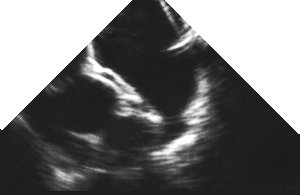

The following pictures show (on the right) an echocardiographic image

of the LV short axis, and on the left, an anatomical image taken from

the visible human project. If you move your mouse over the left image,

then the picture should change to a labelled one, with the right (RV)

and left (LV) ventricular cavities clearly visible, the interventricular

septum (ivs) between, them, and the strangely named inferior, posterior,

and anterior walls of the left ventricle shown (iw, pw and aw respectively)

together with their blood supply. The territory supplied by the left

anterior descending coronary artery is shown in green, that supplied

by the circumflex in red, and the right coronary artery territory in

blue.

The papillary muscles are also labelled (pm = posteromedial, al = anterolateral). (If anything, the anatomical section is a bit too close to the mitral valve, and the papillary muscles are thus smaller in cross section - we've taken this section because in sections nearer the apex, the left ventricular cavity is minuscule). In addition, the left ventricle in the visible human is very poorly filled, so the wall appears thickened, and the cavity diminished. Note that coronary anatomy varies considerably from individual to individual, so the above supply doesn't necessarily apply to everyone. Use the information contained in an angiogram of the patient, if you have this! Obtaining the viewsAs the probe tip passes through the gastro-oesophageal junction, there may be some patient discomfort. Reassure them, then anteflex the probe to keep mucosal contact. The depth of field needs to be increased to adequately view all structures.